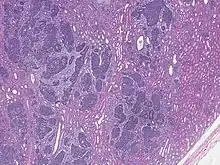

| High magnification micrograph showing the three elements of Wilms' tumor. H&E stain. | |

Pathologically, a triphasic nephroblastoma comprises three elements:[11]

- blastema

- mesenchyme (stroma)

- epithelium

Wilms' tumor is a malignant tumor containing metanephric blastema, stromal and epithelial derivatives. Characteristic is the presence of abortive tubules and glomeruli surrounded by a spindled cell stroma. The stroma may include striated muscle, cartilage, bone, fat tissue, and fibrous tissue. Dysfunction is caused when the tumor compresses the normal kidney parenchyma.

The mesenchymal component may include cells showing rhabdomyoid differentiation or malignancy (rhabdomyosarcomatous Wilms).